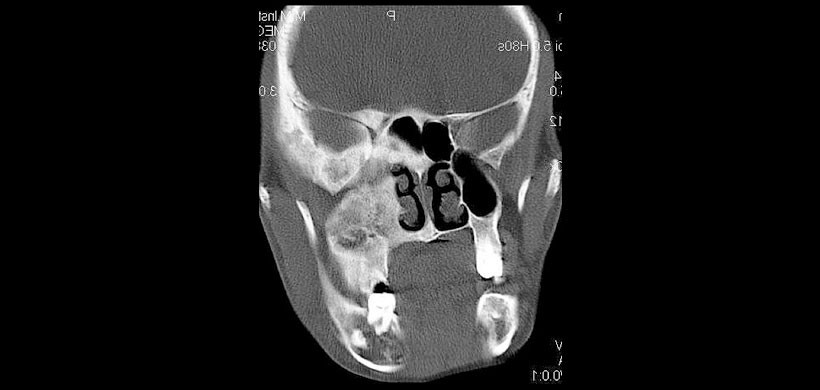

Figura 4: Corte coronal de TC  que revela la lesión que cruza la línea media en la región frontal con afectación de Crista Galli.